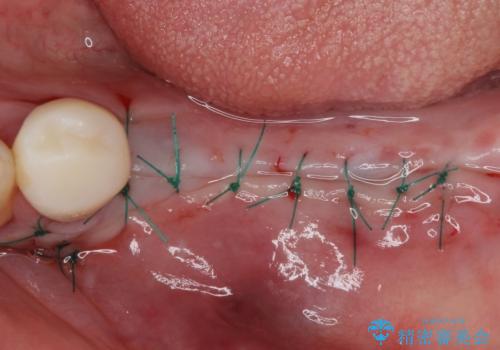

上顎は左右ともに骨が少ない状態であり、特殊なドリルを用いた歯槽骨の拡大や自家骨挙上などを行いながらインプラントを埋入していくこととしました。

右下の銀歯も気になるとのことで、インプラント治療と並行してオールセラミックによるブリッジ補綴治療も行うこととしました。

地元に戻られる前に無事に治療を終えることができました。

今後は東京出張のタイミングでメインテナンスに通院していただきながら、インプラントの状態をチェックしていくことになります。